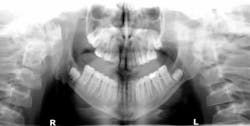

Patient: 14-year-old male

- Patient referred to oral and maxillofacial surgeon to evaluate lower third molars

- Significant, well-circumscribed, expansile radiolucencies around impacted teeth

- Medical history of mental delay

- Recent excision of a basal cell carcinoma from the patient’s chest